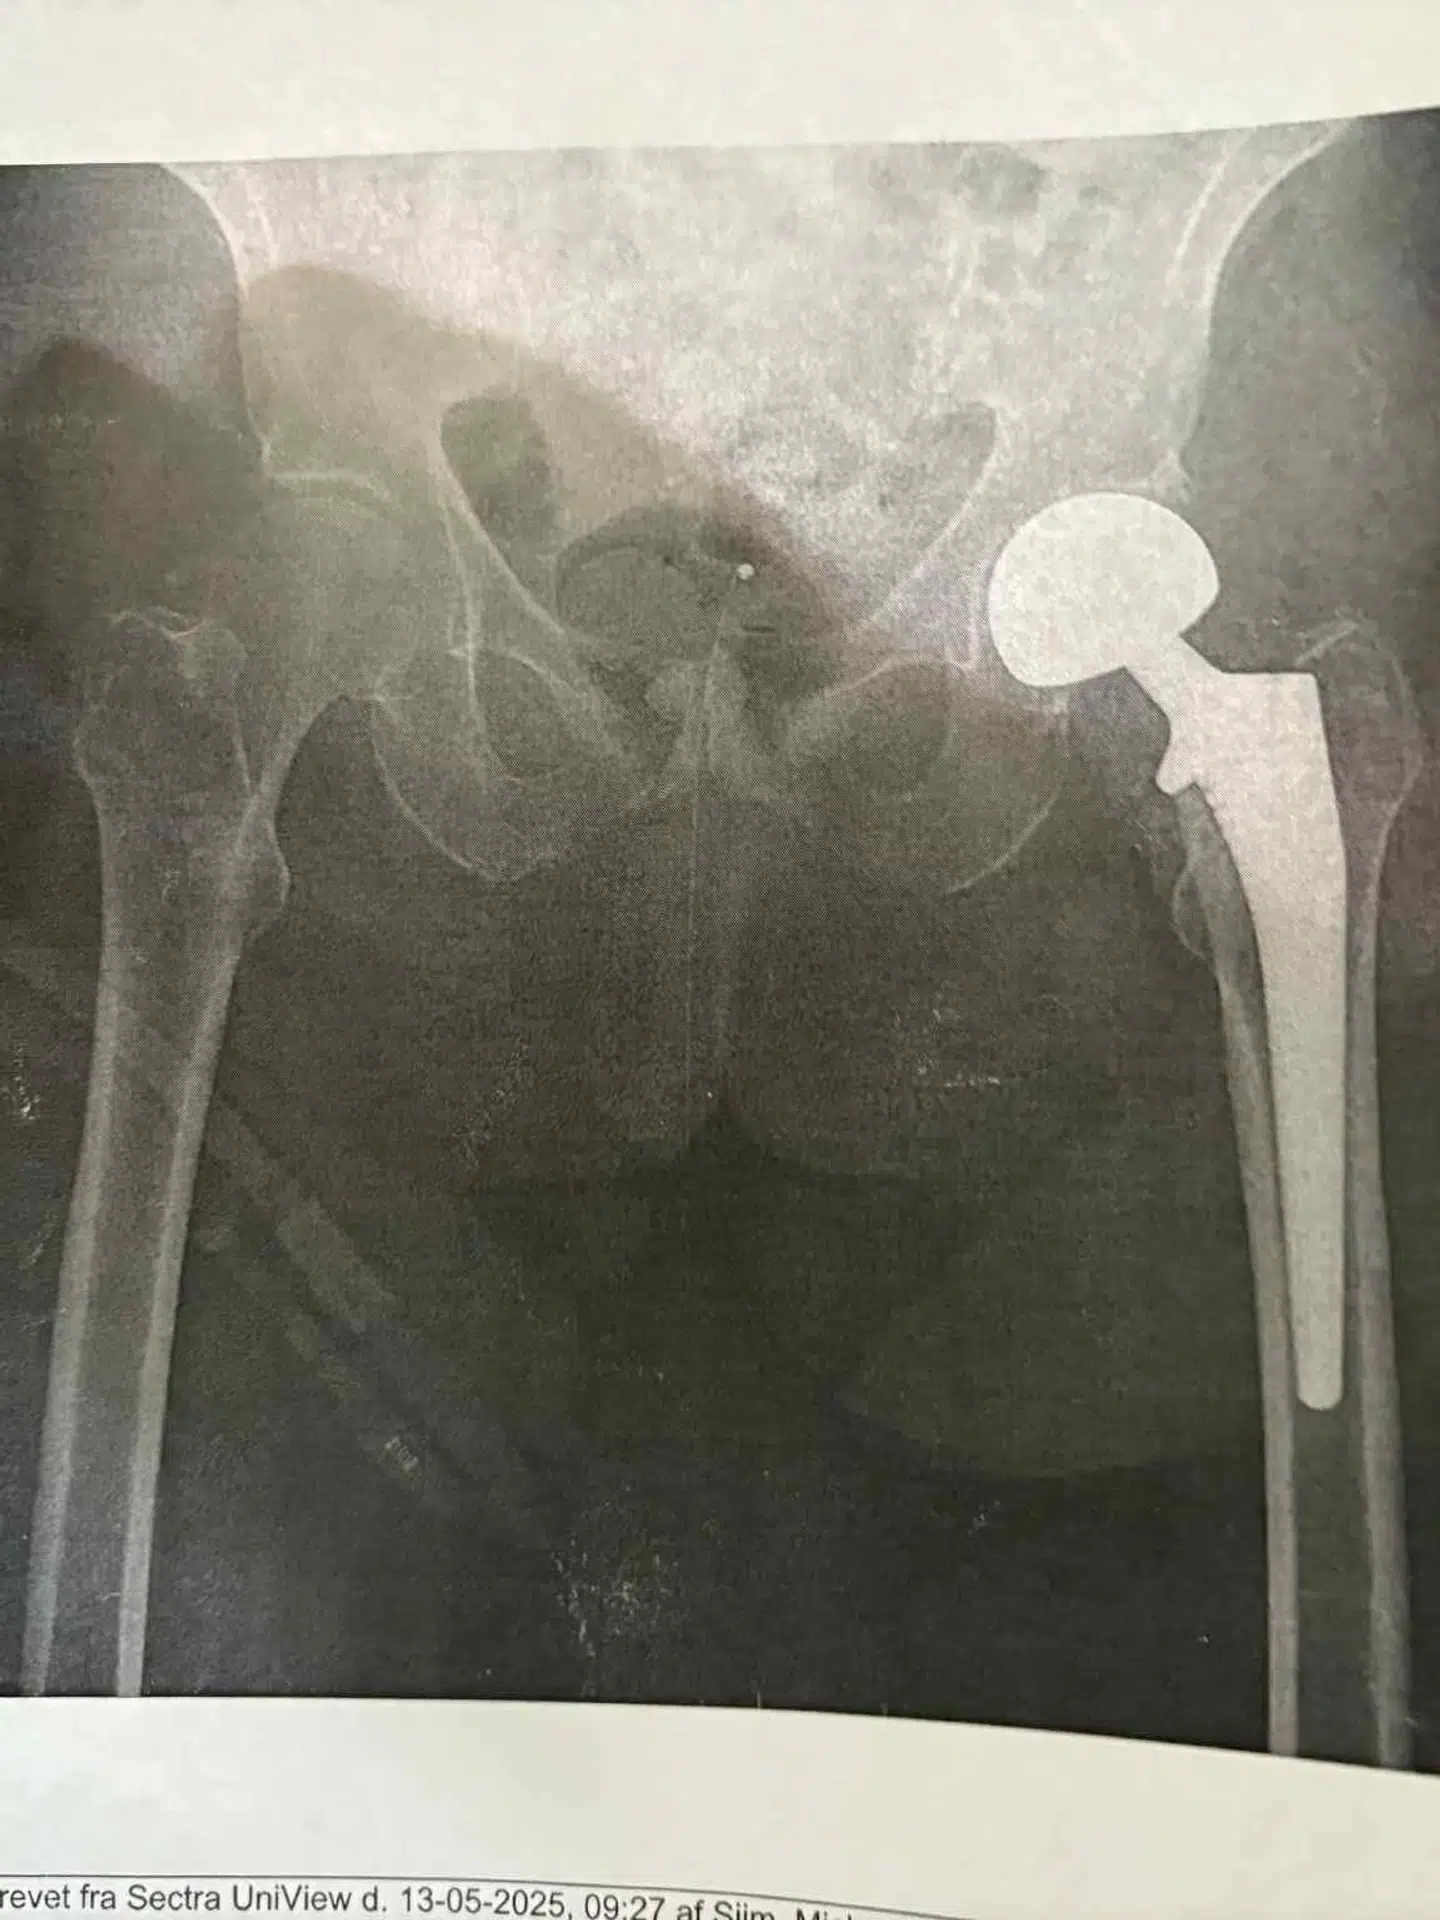

På hospitalet er beskeden ubarmhjertig: En brækket hofte.

Det betyder, at Inge skulle have en ny hofte, ligesom det også har haft den konsekvens, at hun siden har været dårligt gående og haft voldsomme smerter.